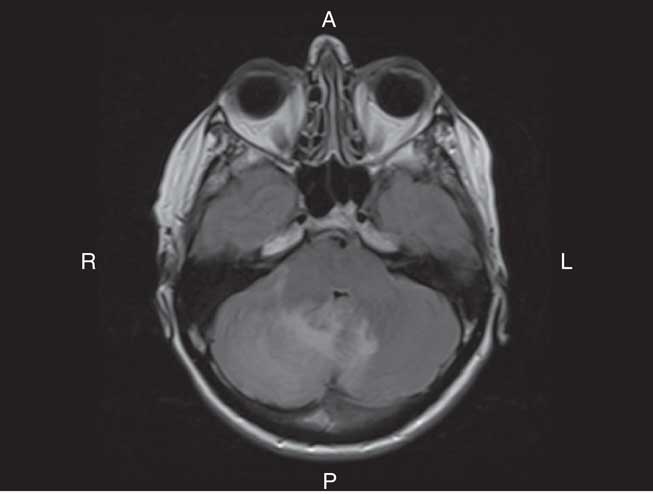

On examination, she had bilateral appendicular ataxia, a positive Romberg sign, and an ataxic gait. The remainder of her examination was normal. CT of her head showed right cerebellar edema. MRI showed cerebellar leptomeningeal enhancement with edema and localized mass effect (Figure 1). Her C-reactive protein and erythrocyte sedimentation rate were elevated at 13.3 mg/L and 25 mm/hour, respectively. Complete blood count (CBC), blood chemistry, creatinine, and glucose were normal. Infectious and inflammatory workups were negative. A CT of the chest, abdomen, and pelvis and a bone scan showed no malignancy.

Figure 1 Axial T2 FLAIR MRI of the brain with Gadolinium showed hyperintensity in keeping with edema within the right lobe of the cerebellum. The edema extended across the vermis into the left cerebellar hemisphere. There was associated regional mass effect on the brainstem and effacement of the fourth ventricle. There was also linear enhancement along the folia of the cerebellum, which was in keeping with leptomeningeal enhancement. The leptomeningeal enhancement was greater on the right than the left.